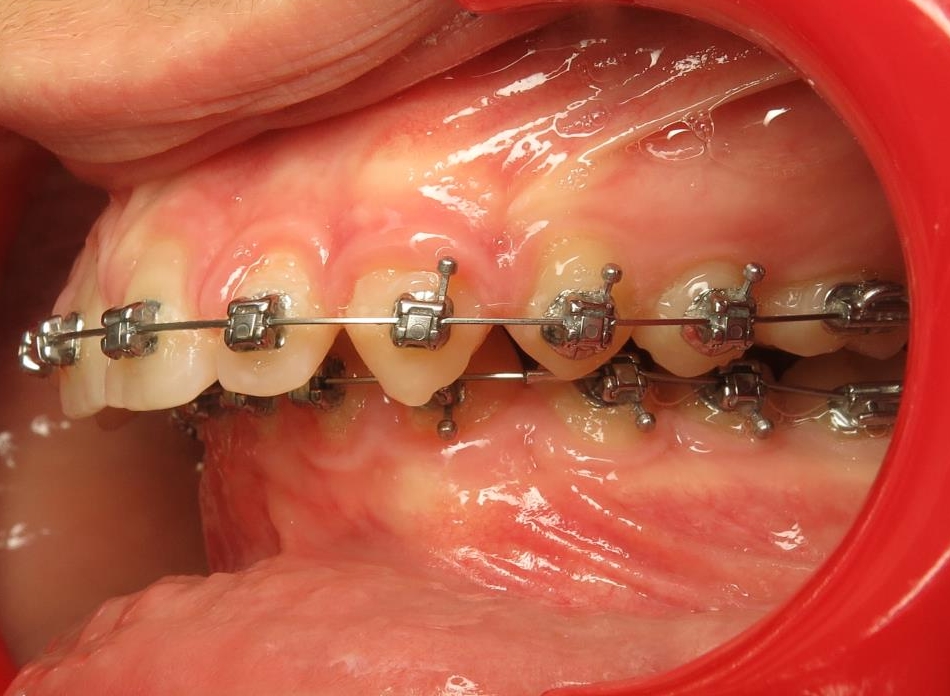

2 - Préparation orthodontique et résultat après chirurgie

Les photos supérieures montrent les arcades juste avant la chirurgie, avec un alignement complet et des axes dentaires physiologiques. La largeur de l’arcade maxillaire a été préparée pour permettre un emboîtement optimal après l’avancée mandibulaire. En bas, les photos post-opératoires montrent des arcades désormais coordonnées, avec une occlusion stable et harmonieuse, grâce à une préparation rigoureuse en amont de l’intervention chirurgicale.